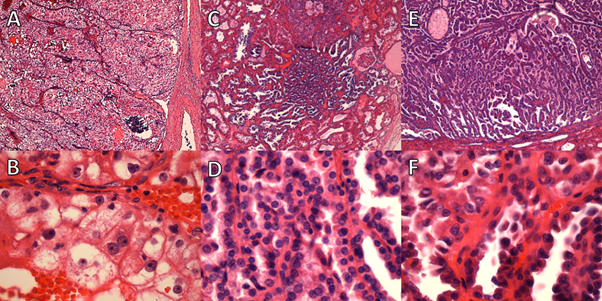

Figure 4

Figure 4. Case 2: A and B. Low-power fields showing clear cell renal cell carcinoma. C. High-power field showing rhabdoid differentiation. D. High-power field showing features consistent with a grade of 4.

Figure 5

Figure 5. Case 2: A-C. Clear-cell tubulopapillary renal cell carcinoma. D-F. Multilocular cystic renal neoplasm of low malignant potential.